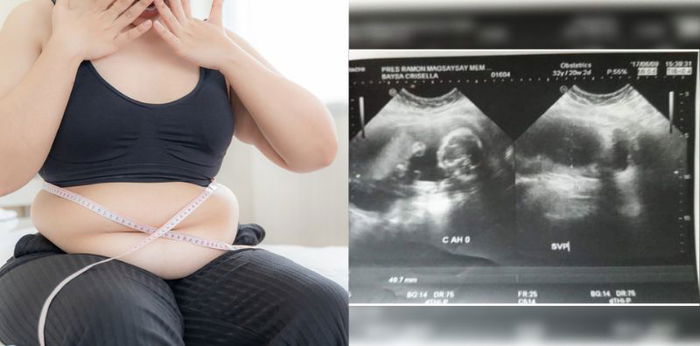

Kaya nagpa-check-up ako at nalaman na masyadong makapal ang lining sa matres ko kaya ako dinudugo ng ganoon. At sinabi nga ng doctor na kailangan kong ma-raspa dahil sa kalagayan ko.

Hanggang sa taong 2017, nalaman ko na sa wakas, nagdadalang-tao na ako!

May mga hindi pa nga naniniwala na buntis ako. Kaya dahil sa mga naranasan kong false pregnancy, inulit ko ang test. Apat na beses akong nag test at lahat positive bago ako nagpa-ultrasound. Nakakataba ng puso na marami ang sumusuporta sa pagbubuntis ko.